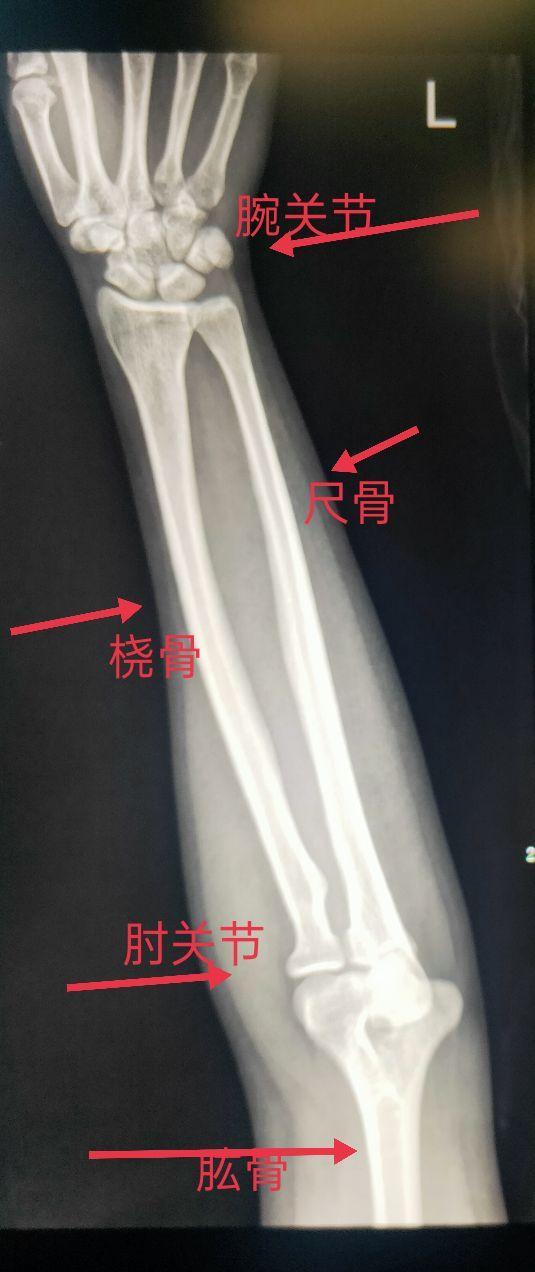

一、尺、桡骨正常解剖

尺骨为前臂的稳定骨,是两根前臂骨中位于内侧且较长的骨,分二端一体。尺骨上端膨大,其上突的鹰嘴呈不整的四方形。它与肱骨滑车下缘相对应,构成肱尺关节。尺骨下端的是尺骨小头和尺骨茎突。尺骨小头与桡骨的尺骨切迹相对应,构成桡尺远侧关节。

桡骨位于前臂外侧部,分一体两端。上端膨大称桡骨头,头下方略细,称桡骨颈,颈的内下侧有突起的桡骨粗隆。桡骨下端前凹后凸,外侧向下突出,称茎突。桡骨茎突和桡骨头在体表可扪到。

三、尺、桡骨X线图像显示

在尺、桡骨正位片上可以看到尺骨、桡骨、肘关节(部分肱骨、鹰嘴窝、肱骨滑车、肱骨外上髁、肱骨内上髁)、腕关节(手舟骨、月骨、三角骨、豆状骨、大多角骨、小多角骨、头状骨、钩状骨、部分掌骨)。